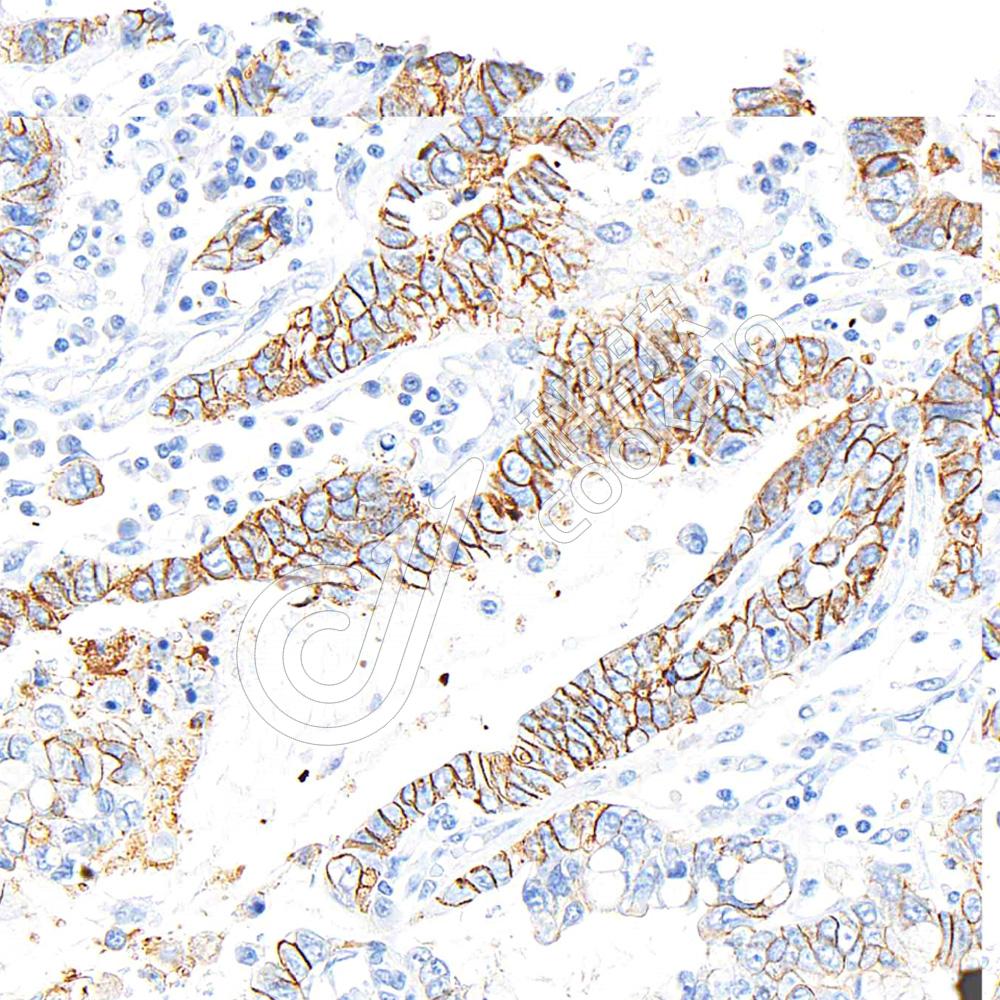

Glyceraldehyde 3-phosphate dehydrogenase (abbreviated as GAPDH or less commonly as G3PDH) is an enzyme of ~37kDa that catalyzes the sixth step of glycolysis and thus serves to break downglucose for energy and carbon molecules. In addition to this long established metabolic function, GAPDH has recently been implicated in several non-metabolic processes, including transcription activation, initiation of apoptosis, ER to Golgi vesicle shuttling, and fast axonal, or axoplasmic transport. In sperm, a testis-specific isoenzyme GAPDHS is expressed.